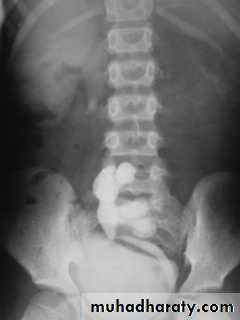

Horse shoe kidney -Kidneys may fail to separate.

-Almost invariably the lower poles remain fused.

-The kidneys axes are more parallel to the spine and malrotated.

-Diagnosis can be made by plain x-ray in some cases.

IVU shows

1. The kidneys at low position .

2.Close to the spine with long axis parallel to the spine .

3. Malrotation manifested by medially directed calyces.

4- The renal pelvis and ureters are anterior and lateral in position .